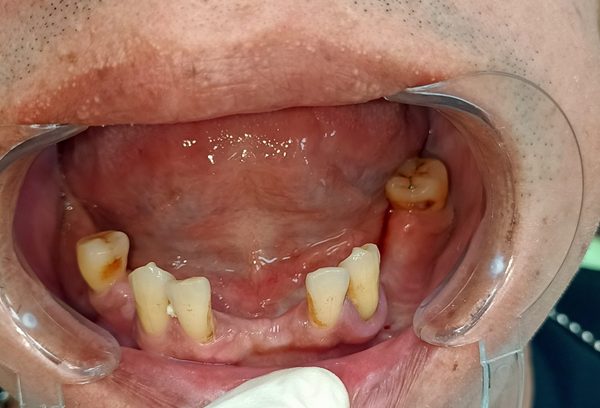

老實說,身為一個小上班族,看著 62 歲的爸爸每天看著想吃的東西不能吃而皺著眉,好像咬一口肉也能把人生咬到困擾深處,真的會心酸。爸爸年輕時抽菸抽得兇,當年覺得「沒事啦,大家都在抽」,結果這些習慣在他退休後開始反撲。牙周開始惡化、牙齒掉掉補補,最後甚至變成多顆脫落。每次吃東西咬一咬,突然跟我說「欸齒套跑掉了啦…」我真的不知道該笑還該擔心。

他也曾做過活動假牙,但不是太鬆、吃到一半滑出來讓他超尷尬,就是太緊讓牙齦痛到爆炸。甚至一個月跑診所兩三趟只是為了微調活動假牙,我看他調到心都累。久了連講話都變得不太敢張嘴,跟朋友聚餐也開始很少出去。身為女兒,看得真的很不是滋味。